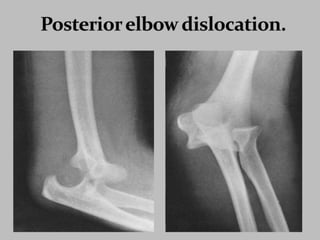

Fracture Classification.

DISTAL HUMERUS:

FRACTURES:

SUPRACONDYLAR

INTERCONDYLAR

CONDYLAR

EPICONDYLAR

FRACTURES OF

PROXIMAL ULNA:

OLECRANON

FRACTURE

CORONOID PROCESS

FRACTURES

OF RADIUS:

RADIAL HEAD

RADIAL NECK